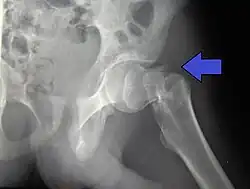

X-rays of the affected hip usually make the diagnosis obvious; AP (anteroposterior) and lateral views should be obtained.